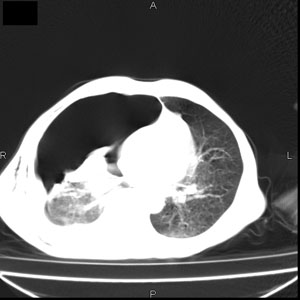

患者男,77岁,于3日前从树上摔下,头部查ct示蛛血,硬膜下出血,上腹部ct未见明显异常,右侧胸腔积液,左侧如常。肺部拍片示右侧肋骨多发骨折住院后今日来查肺部ct,我看到的是1。右侧胸腔血气胸并右肺上叶,中叶压缩性肺不张,2。右肺下叶肺挫伤并多发肋骨骨折,肌内及皮下积气3。左侧少量胸腔积液,我想请教的是3天前左侧胸腔里没有积液今天怎么出现了呢,是什么原因呢?请讨论。

回复楼主   左侧液气胸,液体来源1、肯定有血液成分,多少不一定。2、胸膜腔渗液,由于肺压缩、活动度下降,肯定胸膜吸收有问题,导致积液增多。

因为3天前病人刚摔的时候,左侧胸腔受伤不严重,故而当时没有胸腔积液,但病人受到这么大的伤害,胸膜腔内的液体动态平衡肯定会受到影响,所以过一段时间后才出现胸腔积液。